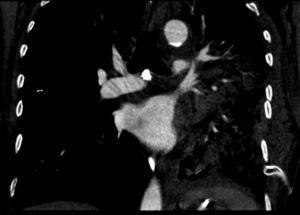

Pulmonary vein obstruction is usually an early complication, occurring during the first few hours after transplantation, and causes severe symptoms. Marked hypoxia, pulmonary edema, and pulmonary infiltrates are observed. If the lower lobe is more severely affected, a high suspicion for such a complication is warranted, and an early additional diagnostic test should be ordered. The initial test should be a transthoracic or transesophageal echocardiogram, in spite of this test being only useful for diagnosis when performed by an experienced operator, due to a challenging visualization and interpretation after recent surgery 6. Alternatively, chest CT angiography can be used, which also allows artery suture and distal vascularization to be assessed and reconstructions to be produced. CT angiography establishes the diagnosis in most cases. Anticoagulation using heparin and clinical course monitoring is used to manage partial thromboses and stenoses. In the event of a complete vein obstruction or a poor course, in patients with a very recent surgery, re-transplantation or lobectomy for double-lung transplantations, may be needed. If the patient is in a stable condition, several days have elapsed, and anatomic characteristics are favorable, an angioplasty with dilation and stent implant can be considered.

Arterial suture complications are usually less common and are found later. They result in persistent hypoxia and pulmonary hypertension. Diagnosis is based on CT angiography and/or arteriography. Some degree of arterial suture stenosis with no clinical significance is commonly found in CT angiography, due to donor-receptor size discordance or to the suture itself. Significant stenoses are due to kinking or thrombosis at the suture level. The former are usually treated win angioplasty and dilation, whereas usual therapy for the latter is stent implant if required. Anticoagulation is used for thrombotic cases 7.

Figure 3. Coronal view in CT angiography showing complete lower pulmonary vein obstruction after left lung transplantation.